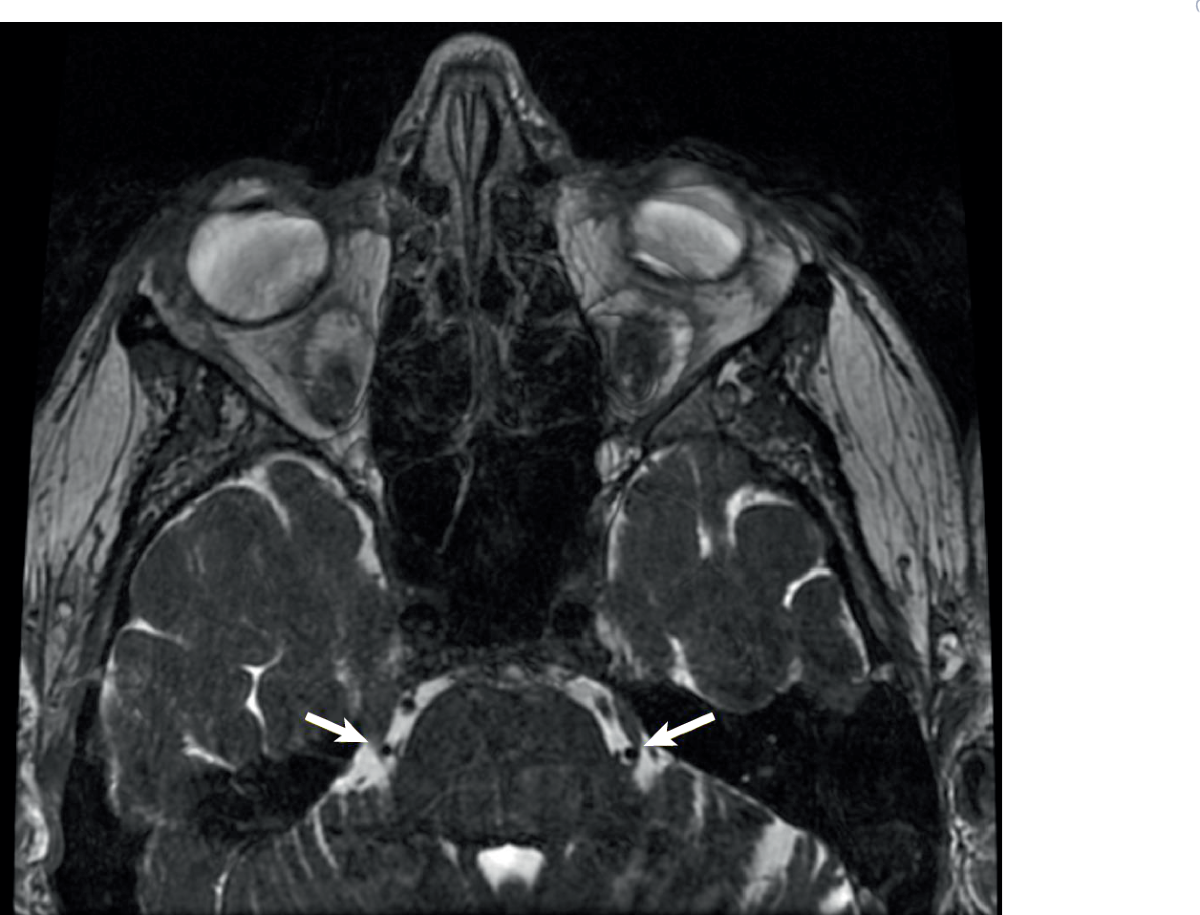

Trigeminal Nucleus Mri

Trigeminal Nucleus Mri CT Guided Gasserion Ganglion Block - Precise Saviour